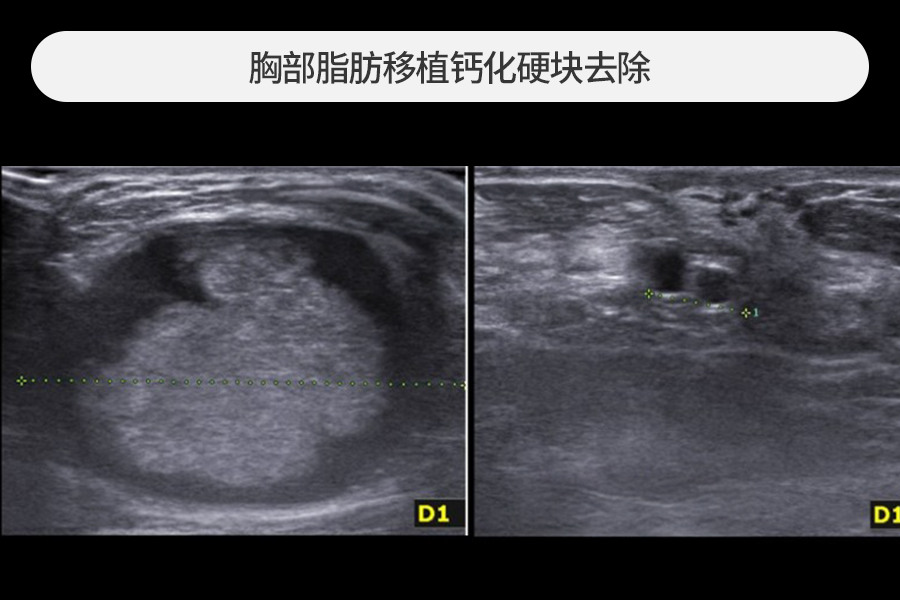

4~5cm 大小的脂肪移植硬块去除

该患者因胸部脂肪移植后摸到乳房硬块而来院,观察到4~5cm大小的巨大钙化硬块。

尺寸较大的脂肪移植硬块发生急性炎症时风险较高,需要尽快去除。

在超声引导下保留正常组织,仅安全去除了硬块。